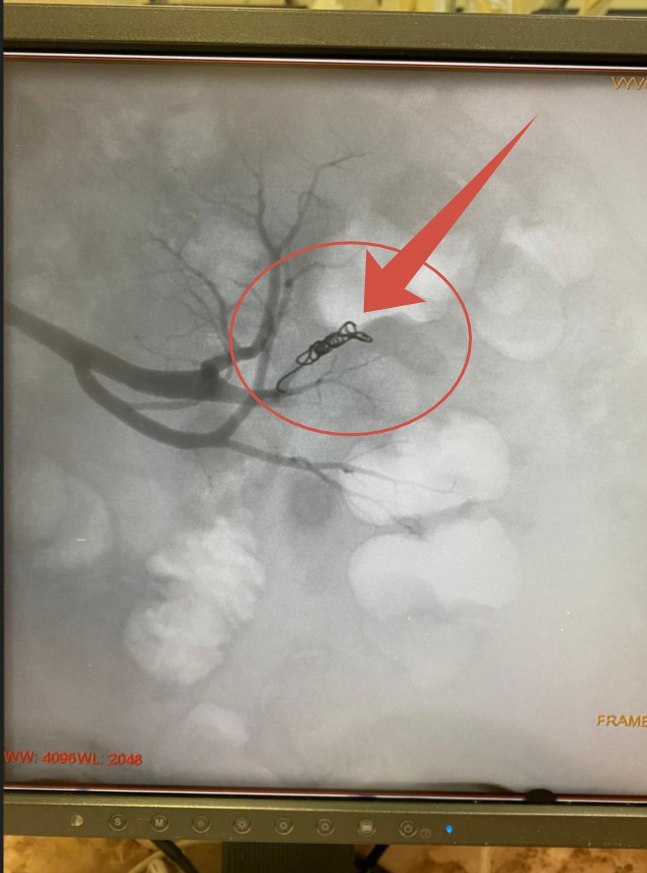

Используя современные методики и опираясь на наличие передового оборудования и свой практический опыт, рентгенэндоваскулярные хирурги в ходе внутрисосудистого вмешательства обнаружили источник кровотечения. Им оказалась одна из веточек почечной артерии. Врачи провели её эмболизацию, тем самым радикально прервав кровотечение.